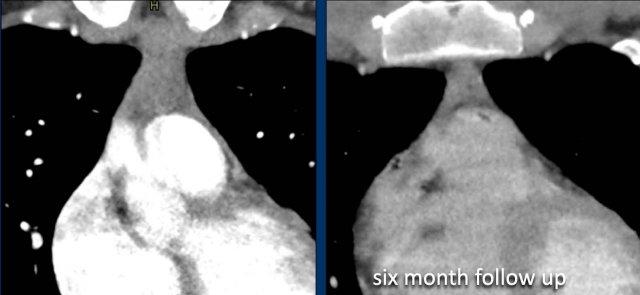

Các hình ảnh này của một phụ nữ 24 tuổi, mắc u xương (osteosarcoma) và được điều trị bằng hóa trị liệu.

Hình ảnh

Tại thời điểm bắt đầu điều trị, tuyến ức có biểu hiện tăng sản.

Tại thời điểm theo dõi 10 tháng, tuyến ức bị teo nhỏ.

Hai năm sau, xuất hiện tăng sản tuyến ức dội ngược.